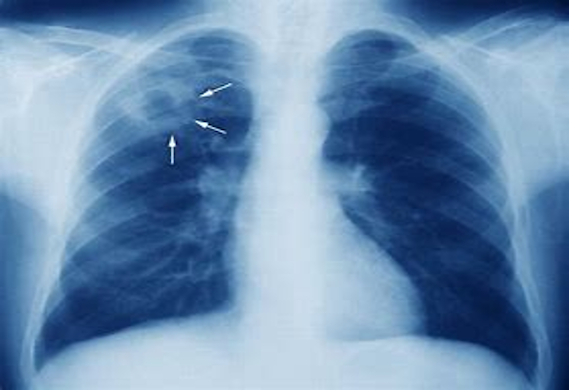

Spectrum and Correlation of Clinical, Radiological and Biochemical Parameters in Tuberculosis in a Hospital in South India

The objectives of the study were to describe various comorbidities in patients with tuberculosis, determine expected radiological presentations in these patients and to determine prognosis altering metabolic indicators in patients with TB